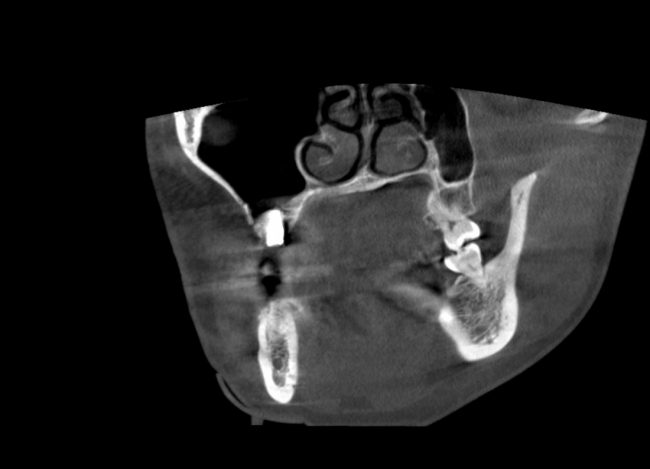

Если сделать КЛКТ на этом этапе (через 2-3 недели после операции), то иногда мы можем увидеть утолщение слизистой оболочки в области дна альвеолярной бухты, вплоть до рентгенологической картины гайморита:

однако, в течение последующего месяца (при соответствующей терапии) рентгенологическая картина возвращается к нормальной: